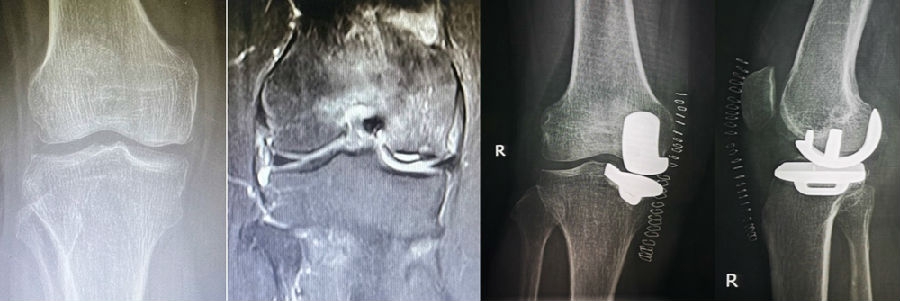

病例1:女,61岁,右膝关节诊断为Koshino Ⅲ期SONK,行右膝内侧单髁手术治疗。

(4)Koshino Ⅳ期SONK

由于存在继发退行性改变,一般不建议单纯行膝关节镜+自体骨软骨移植术。需在考虑5个因素的基础上兼顾患者年龄、性别和活跃程度,分别选择膝关节镜+HTO术+微骨折术、膝关节镜+HTO+坏死区病灶刮除+自体植骨术或单髁置换术。对于合并症状性髌股关节炎、外翻畸形、坏死区范围大影响单髁假体稳定性等的Koshino Ⅳ期膝关节股骨内侧髁SONK,采用全膝关节置换术。

病例2:女,81岁,行内侧单髁手术治疗,术后恢复良好。

综上,膝关节股骨内侧髁自发性骨坏死的阶梯治疗应遵循下图的治疗原则。